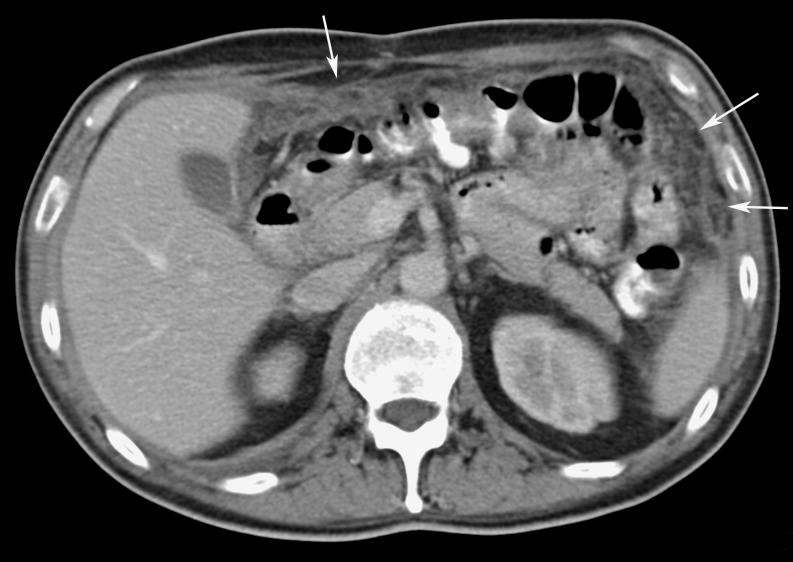

Omental cakes typically are associated with ovarian carcinoma, as this is the most common malignant aetiology. Nonetheless, numerous other neoplasms, as well as infectious and benign processes, can produce omental cakes. METHODS: A broader knowledge of the various causes of omental cakes is valuable diagnostically and to direct appropriate clinical management. RESULTS: We present a spectrum of both common and unusual aetiologies that demonstrate the variable computed tomographic appearances of omental cakes. CONCLUSION: The anatomy and embryology are discussed, as well as the importance of biopsy when the aetiology of omental cakes is uncertain.